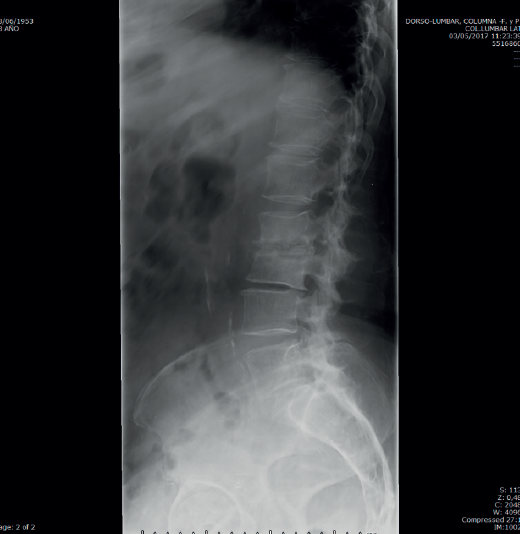

Figura 3. Radiografía a los 3 meses del ingreso inicial.

La analítica se había normalizado. En la radiografía lumbar (Figura 3) se veían signos de discopatía grave.